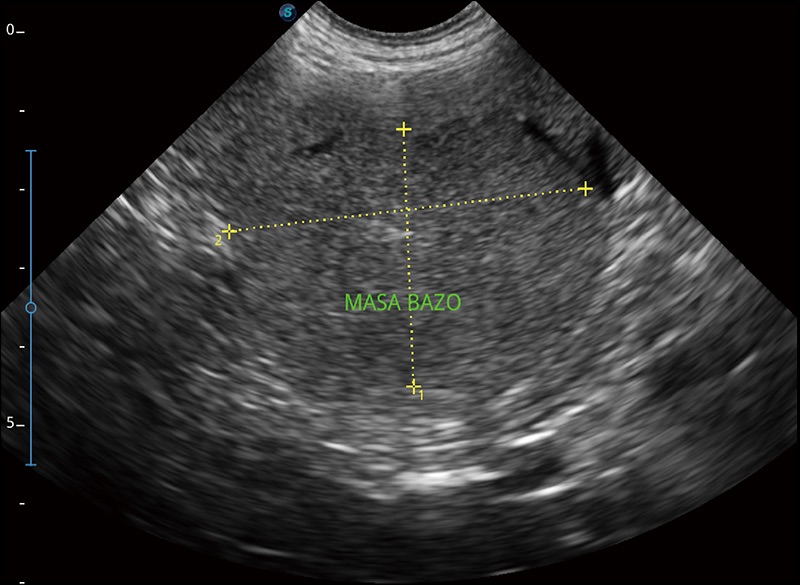

扩展成像

支持线阵和凸阵探头,一键操作即可获得更宽的图像视野